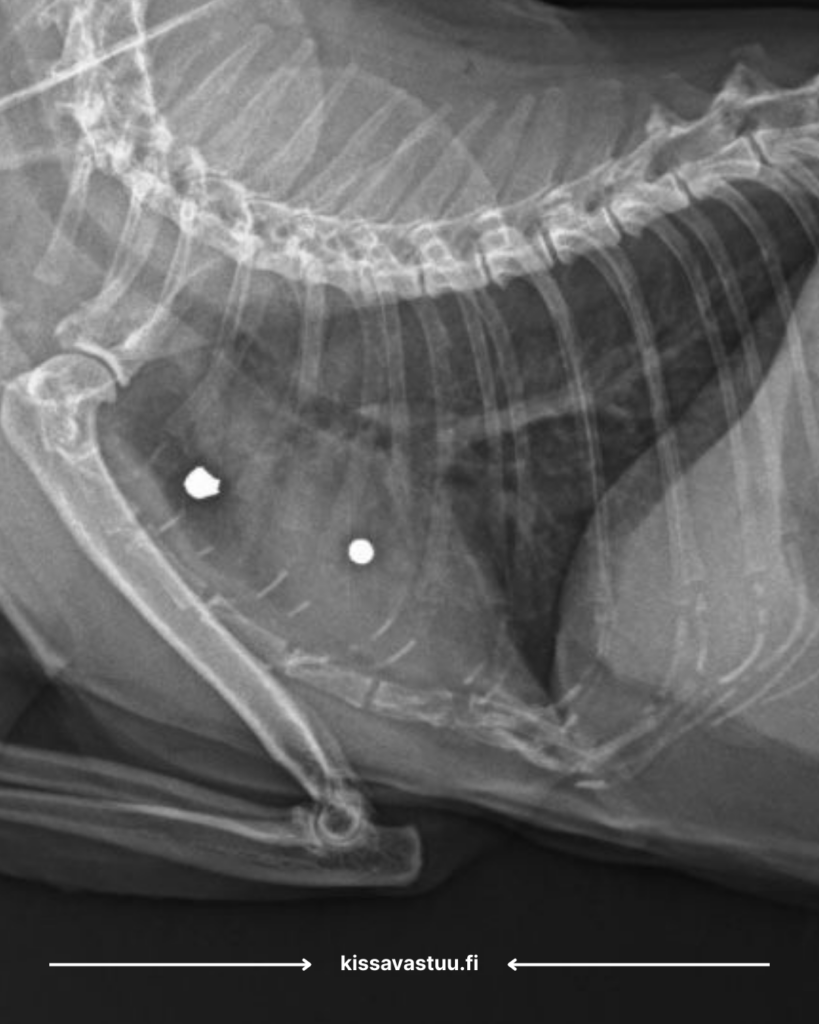

Allu ei ollut silloinkaan nuori kissa, kun adoptoin hänet ja nyt kuusi vuotta myöhemmin ajattelin, että olisi hyvä röntgenkuvata luusto. Shokki oli aikamoinen, sekä eläinklinikan henkilökunnalle, että varsinkin minulle itselleni, kun kuvista paljastuikin, että kissaani on ammuttu.

Allun onni on se, että hän ensinnäkin selvisi hengissä ja toiseksi se, että tällä hetkellä voimme vain jäädä seuraamaan tilannetta eikä tarvitse ryhtyä esimerkiksi leikkausoperaatioihin.